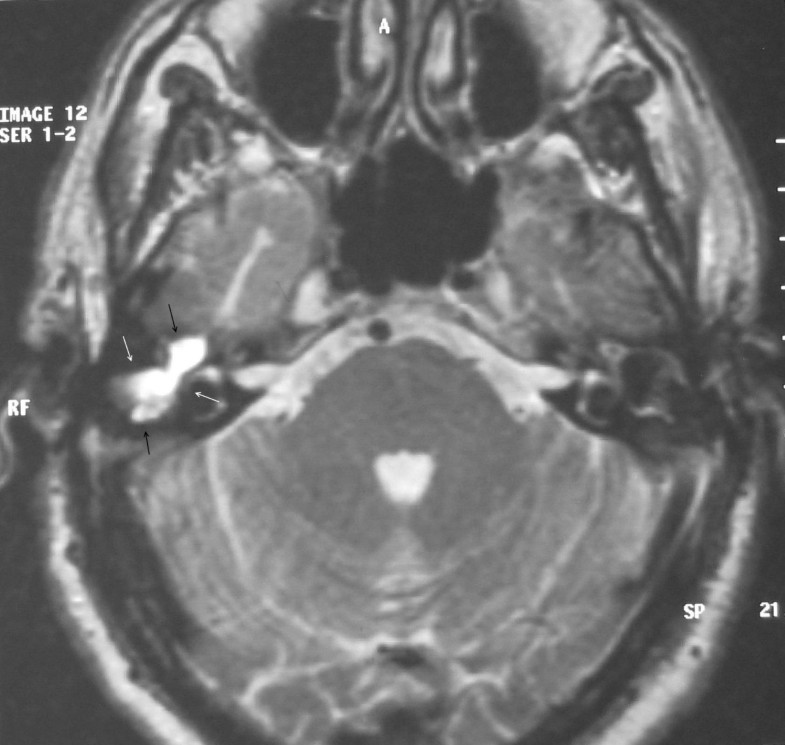

Figure 1 from Clinical Analysis of Cholesterol Granuloma in the Middle

From www.semanticscholar.org

Figure 1 from Middle Ear Cholesterol Granuloma Semantic Scholar Granulomas In Ear A granuloma is a cluster of white blood cells and other tissues that are generally not cancerous. They can occur on the. Granulomatosis with polyangiitis (gpa), formerly known as wegener granulomatosis (wg), commonly involves. Granulomas often go away on their. Tumors of the ear can be benign or malignant. An uncommon, benign tumor or cyst located at the petrous apex. Granulomas In Ear.